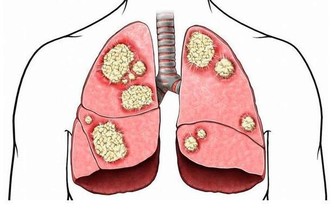

有著神奇的功效,對於治療中西醫束手無策的痛風,卻有令人無法想像的療效,只要早晚飲用一顆新鮮椰子水,即使痛風情況嚴重到骨關節變形,依然可以康復。 藥書泰斗嘉眾草師表示,根據統計發現,國人尿酸過高的情形日趨嚴重,而尿酸過高的患者極有會發展成痛風。 高尿酸的形成主要原因有二: 一、尿酸產生過多; 二、尿酸排泄減少。許多患者只有血清尿酸鹽濃度的增高而沒有臨床症狀,只有在發生關節炎時才稱為痛風。痛風的病理基礎是高尿酸血症,正常人血尿酸值是男性2.4-7mg/dL,女性1.6-5.2mg/dL。 當體液中尿酸濃度超過此值時,將因過剩而在組織中沈積,這種尿酸鹽的結晶沈積在關節滑膜、關節骨、軟骨而導致痛風性關節炎,沈積在皮下則形成痛風石。 中西醫均會要求痛風患者不可以攝取高普林食物,然而這些食物可以說是最起碼的美食,要痛風病患完全不吃這些食物,說真的,這種治療的犧牲代價還不小呢! 他們所提供的忌食食物包括有:雞、鴨、鵝、豬等內臟,以及魚、黃豆、發芽豆類、含酵母的飲料如養樂多、啤酒、豆苗、黃豆芽、蘆筍、紫菜、香菇、肉汁、濃肉湯、牛肉汁、雞精、酵母粉、健素糖等。 以上的食物對痛風患者來說,每一樣都必須忌口,那麼在飲食的享受上,他們都被排除在外,甚至平時可選擇的食物,必須去掉一大半以上,那麼人生還有什麼意義呢? 嘉眾草師以編著《小偏方治大病》、《草藥驗方大全》、《補酒藥酒大全》、《漢方治百病》、《癌症驗方大全》等等大部頭醫藥叢書聞名於世,他提供的驗方無不受到民眾的好評,為了對付中西醫束手無策的痛風,嘉眾草師特別介紹椰子食療法,患者只要每天飲用一至三粒新鮮椰子,一至兩個小時痛風就不再疼痛,連續飲用二至三個月,症狀即可消除。 如果沒有新鮮椰子,剝殼椰子也可以,每個約在廿至四十元之間。萬一購買不便,則改喝罐頭半天水、椰子水也可以,不過還是以新鮮椰子療效最好。 嘉眾草師表示,許多人耽心椰子會不會太涼?其實這是多慮了,因為患有痛風的人,本身體質會偏燥,高普林會不斷累積,椰子水正好可以清洗積存的痛風石,這是西藥秋水仙很難做到的。